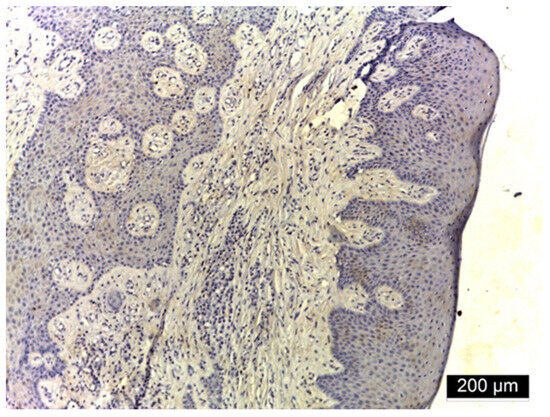

3.3. MMP-2 Immunoreactivity

4.2. MMP-2 Immunoreactivity